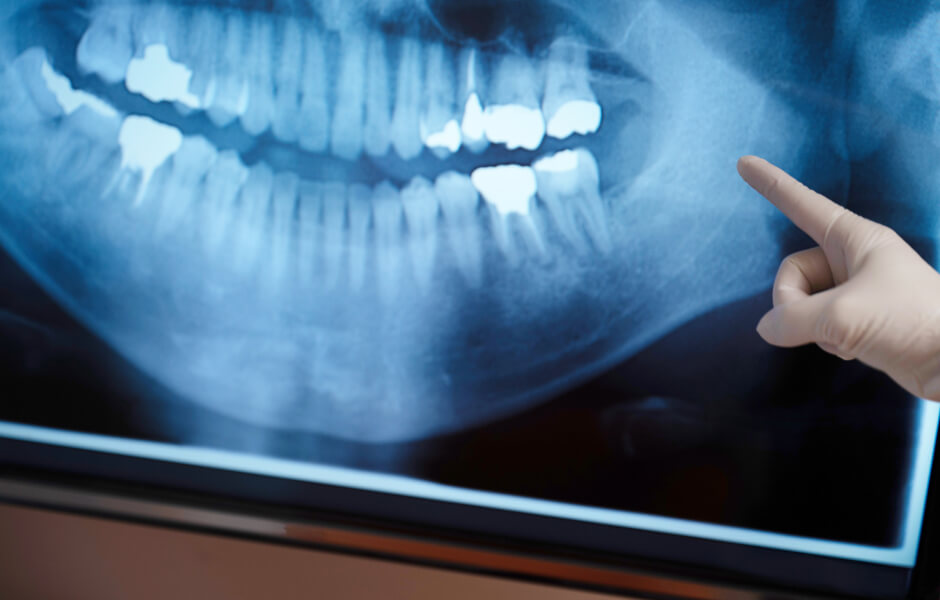

虫歯や歯周病といった歯のトラブルは、日本人が歯を失う最も多い原因です。一般歯科では虫歯や歯周病、歯痛や歯茎の腫れなど一般的な歯科治療を行います。また健康な歯を守る予防歯科や親知らずの抜歯など保険適用される歯科治療の総称を一般歯科といいます。当院と一緒に歯の健康づくりを始めませんか?

一般歯科とは?

なかたに歯科クリニックでは、歯を削る、歯を抜くといった治療を極力避け、ご自身の歯を残す事が何より大切だと考えます。ご自身の歯磨きなど日々のケアだけでは、健康な歯を残すことは困難で、歯のプロフェッショナルである歯医者での定期検診や予防歯科を受診する事は必要不可欠です。歯医者と一緒に健康な歯を守る習慣を身につけましょう。